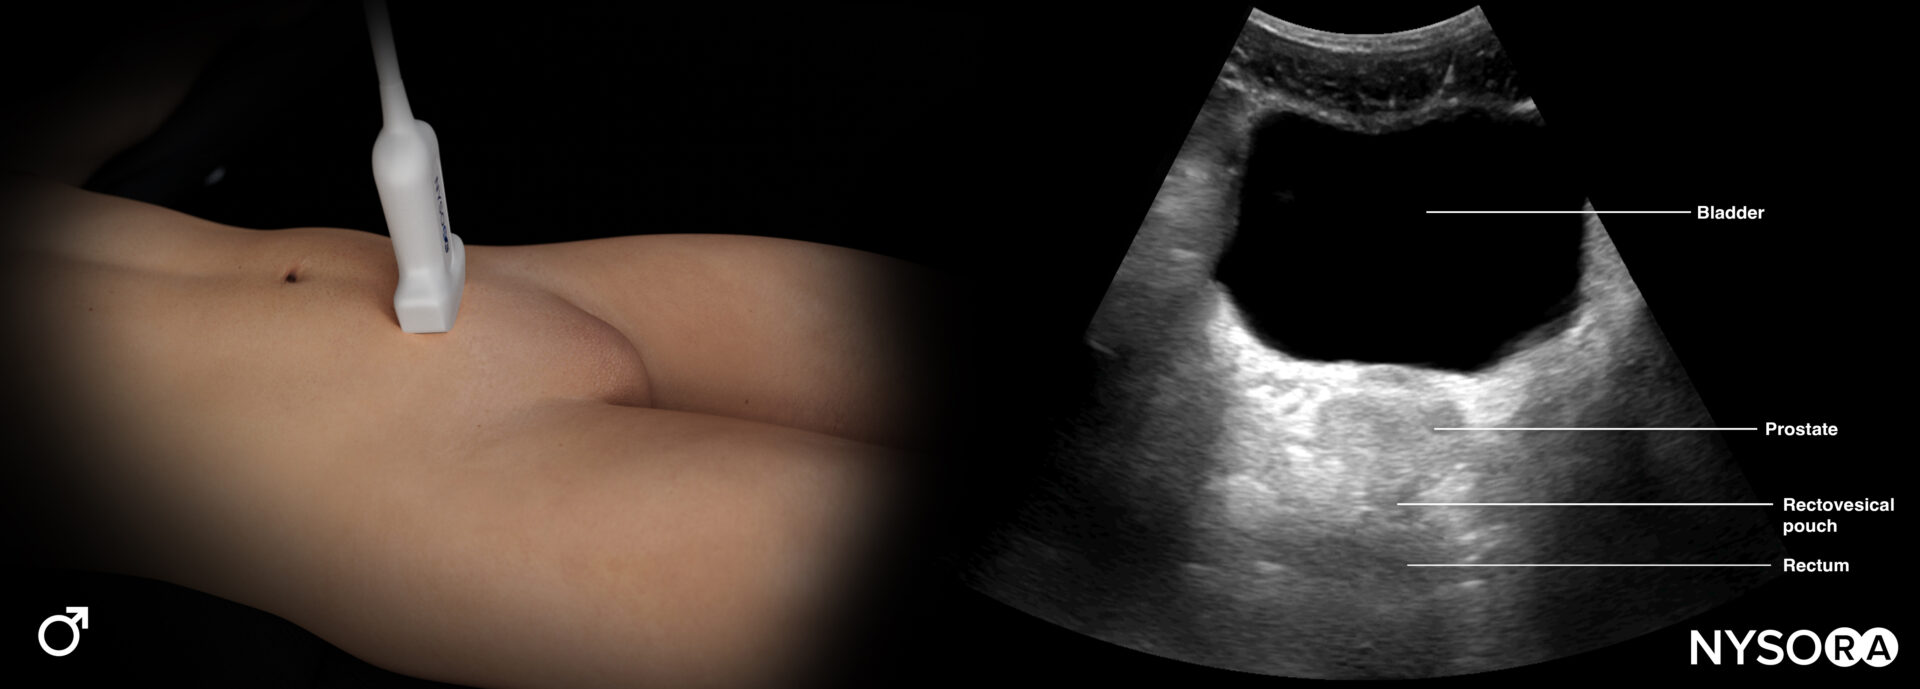

This view assesses the presence of free fluid in the pelvis.

- Position the transducer just above the pubic bone in the midline between the umbilicus and the pubic bone.

- The bladder can be used as an internal anatomical landmark to scan the area behind and lateral to the bladder for free fluid (the rectovesical pouch in men and the rectouterine pouch, or pouch of Douglas, in women).

- Step 1: Longitudinal view (orientation marker toward the head)

Sonoanatomy of interest in males:

Transducer position and ultrasound anatomy of the male pelvis.

Pelvic free fluid collects behind the bladder or the area lateral to the bladder (rectovesical pouch in men and the rectouterine pouch or pouch of Douglas in women).